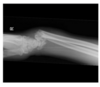

Normal XR elbow

Radial head dislocation

Classification of supracondylar fractures

Supracondylar fracture (Gartland 1 - minimally displaced)

108

Supracondylar fracture (Gartland 3 - displaced, complete)